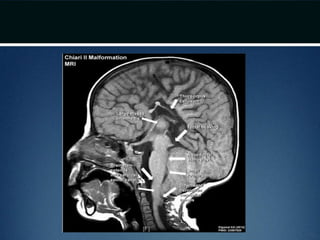

Chiari II malformation

• Caudal displacement of cerebellar vermis, lower

brainstem and fourth ventricle seen exclusively in

patients with myelomeningocele

• Numerous other anomalies associated in various

combinations

– vertical straight sinus

– large venous lakes in the tentorium

– fenestrations in falx, which is often not well formed – gyri

of left and right hemispheres interdigitate – “Chinese

lettering” on axial MRI

Chiari II malformation •Caudal displacement of cerebellar vermis, lower brainstem and fourth ventricle seen exclusively in patients with myelomeningocele • Numerous other anomalies associated in various combinations – vertical straight sinus – large venous lakes in the tentorium – fenestrations in falx, which is often not well formed – gyri of left and right hemispheres interdigitate – “Chinese lettering” on axial MRI